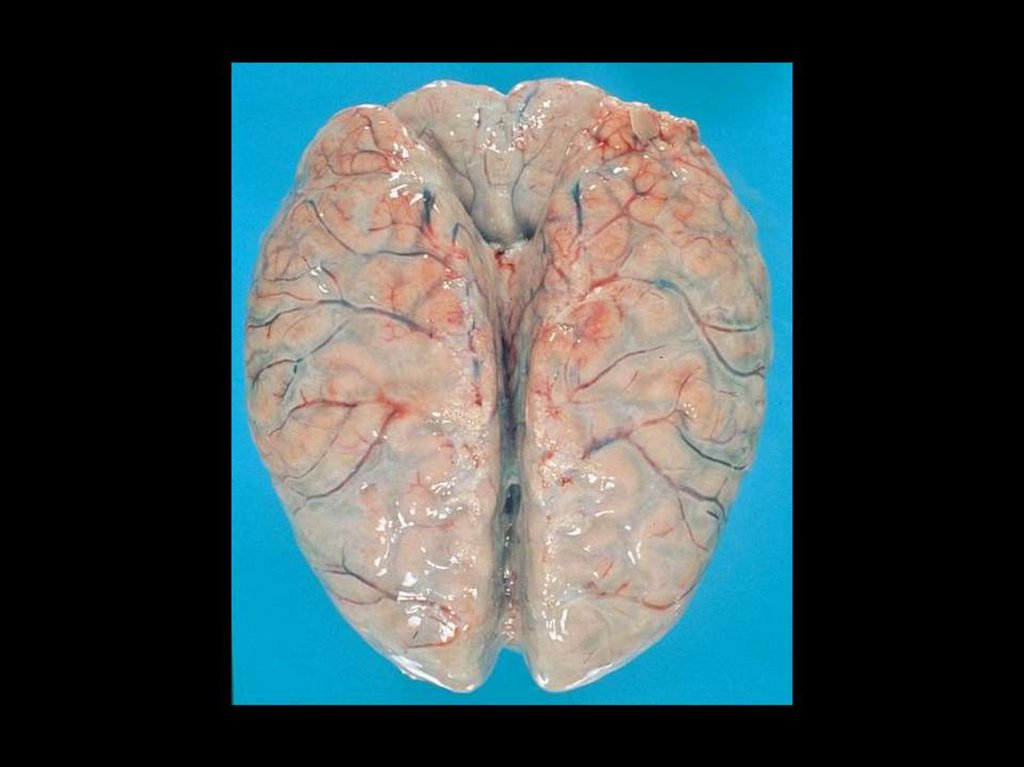

Критерии раннего прогноза осложненного течения БГМ, в т.ч. летального исхода заболевания

Шок при фулминантной форме МКЕ

Некоторые маркеры шока при ФФ МКЕ

Фазы ИТШ

Клинические проявления ДВС-синдрома